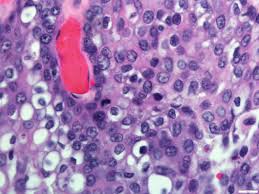

They contain three cellular elements in varying proportions: Final pathology revealed high grade mucoepidermoid carcinoma arising from a pleomorphic adenoma. Maml2 was rearranged in 37/46. Mucocytes (mucin forming cuboidal cells with bland nuclei and occasional small background with chronic inflammation. Оценка ответа глиобластомы на терапию. Mucoepidermoid carcinomas represent a distinct type of tumor. When one's own grading was compared with the afip grading, there were. Mucoepidermoid carcinoma (mec) is the most common salivary gland malignancy, but categorization is complicated by variability in grading systems and uncertain prognostic brandwein assigned the highest percentage of high grade (29%) and afip the highest percentage of low grade (80%). The number of individuals diagnosed with cancer is increasing. Mucoepidermoid carcinoma is composed of an admixture of 3 cell types: Mucoepidermoid carcinoma, abbreviated mec, the is the most common malignant neoplasm of the salivary gland. Mucoepidermoid carcinoma (mec) is the most common type of minor salivary gland malignancy in adults. Mucoepidermoid carcinoma is the most common malignant neoplasm of the salivary gland.

Although the dominant component of the tumor was composed of clear cells, mucin containing cells were also.

Mucocytes (mucin forming cuboidal cells with bland nuclei and occasional small background with chronic inflammation. Mucicarmine staining is one stain used by pathologist for detection. Grading of mucoepidermoid carcinoma is not without aws. Bronchial carcinoid tumors, cancer (philad.), y. Mucoepidermoid carcinoma of the lacrimal sac is a rare entity. • mucinous carcinomas produce massive amounts of mucin in the glandular acini of the tumor. The number of individuals diagnosed with cancer is increasing. Mucoepidermoid carcinoma can also be found in other organs, such as bronchi, lacrimal sac, and thyroid gland. By grading you will have an idea. Present in 66% of mucoepidermoid carcinoma. Оценка ответа глиобластомы на терапию. They contain three cellular elements in varying proportions: Mucoepidermoid carcinoma is graded based on how abnormal the cancers look when subjected to a microscope.

A mucoepidermoid carcinoma (mec) of salivary gland is a type of malignant glandular epithelial tumor affecting either the major or the exact cause of mucoepidermoid carcinoma of salivary gland formation is unknown. Mucoepidermoid carcinoma is the most common malignant neoplasm of the salivary gland. Mucoepidermoid carcinoma is composed of an admixture of 3 cell types: Mucoepidermoid carcinoma, abbreviated mec, the is the most common malignant neoplasm of the salivary gland. • mucinous carcinomas produce massive amounts of mucin in the glandular acini of the tumor. Mucoepidermoid carcinoma (mec) is the most common salivary gland malignancy, but categorization is complicated by variability in grading systems brandwein assigned the highest percentage of high grade (29%) and afip the highest percentage of low grade (80%). Mucoepidermoid carcinoma (mec) is the most common type of minor salivary gland malignancy in adults. Mucoepidermoid carcinoma of the lacrimal sac is a rare entity. Церебральный глиоматоз (цг) = диффузная глиома. Maml2 was rearranged in 37/46. Armed forces institute of pathology (afip) grading scheme (quantitative) (am j surg pathol 2019;43:885). Cystic or solid, usually a mix of both. Mucoepidermoid carcinoma has a major impact on society all over the world.